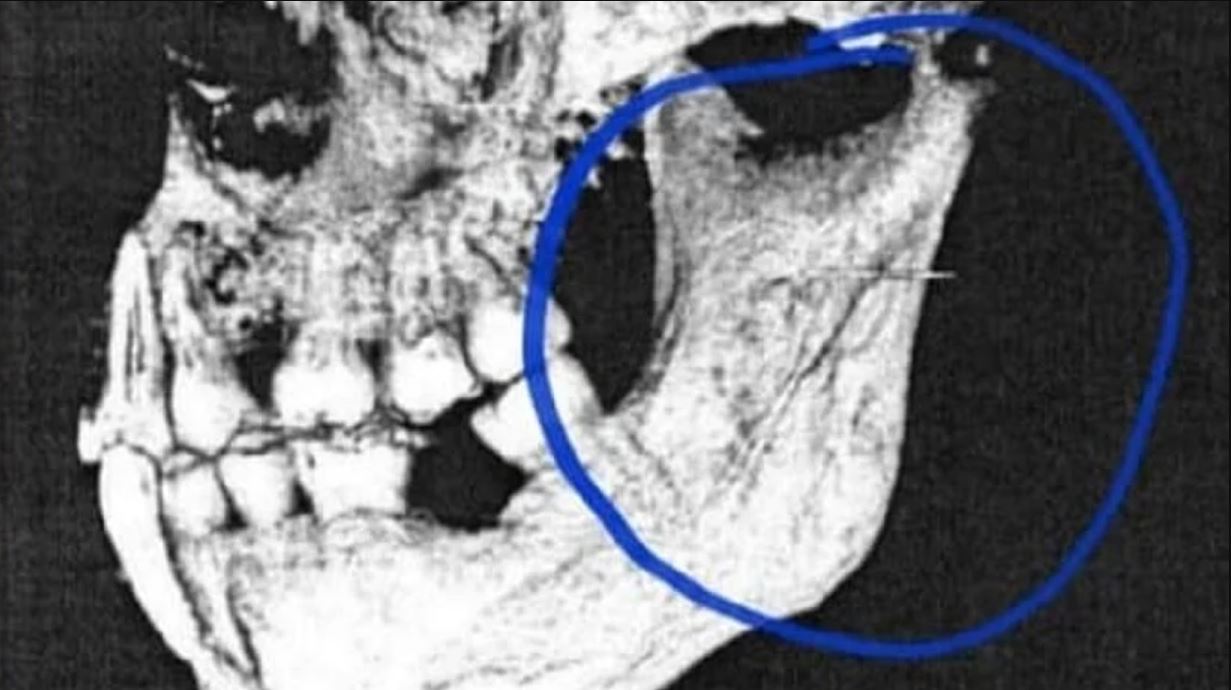

La justicia también determinó que cuando el médico le aplicaba anestesia a la paciente "se rompió la aguja, quedando alojada en el interior de la mandíbula de la demandante (...) atravesando el espesor del músculo pterigoideo lateral y el extremo dorsal, sobrepasa el contorno posterior de la rama mandibular, lo cual obviamente le causa dolor físico a la demandante y un consecuente tratamiento para su extracción, no contemplado en el tratamiento inicial".